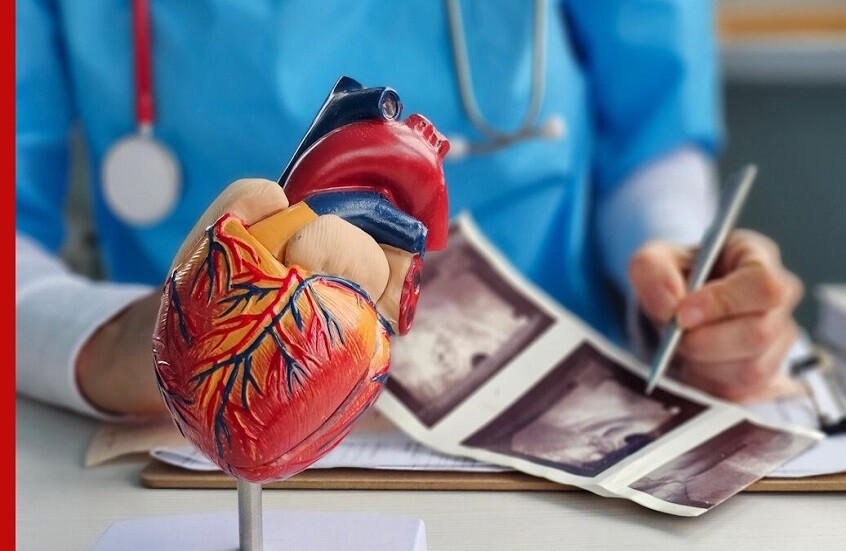

تقنية نانوية روسية تشخص النوبة القلبية خلال 6 دقائق فقط

طوّر باحثون من روسيا جيلا جديدا من الاختبارات السريعة لتشخيص احتشاء عضلة القلب (النوبة القلبية)، وبإمكان هذا الاختبار اكتشاف المرض في ست دقائق فقط.

ومع ذلك، تفوق حساسية الاختبار الجديد نظائره الحالية بنحو 45 ضعفا، وفقا لما أفادت به وكالة "تاس" نقلا عن الخدمة الصحفية لمعهد موسكو للفيزياء والتقنيات.

وقال كبير الباحثين في معهد الفيزياء العامة التابع لأكاديمية العلوم الروسية، أليكسي أورلوف:

"لطالما واجهت الاختبارات السريعة معادلة صعبة: إما السرعة والبساطة، أو الدقة. لكننا تمكّنا من تجاوز هذه المفاضلة جذريا، إذ لم نعمل على تحسين العلامات التقليدية فحسب، بل استبدلناها بسلاسل نانوية تنشط داخل مجال مغناطيسي دوّار".

وأوضح أورلوف وزملاؤه أن سرعة تشخيص احتشاء عضلة القلب تؤثر بشكل مباشر في فرص نجاة المريض، إلا أن الطرق المخبرية الحالية تستغرق ما بين 30 و60 دقيقة، وتتطلب معدات خاصة وكوادر مؤهلة. كما أن الاختبارات السريعة المتاحة غالبا ما تعطي نتائج سلبية كاذبة بسبب انخفاض حساسيتها، ما يحدّ من فعاليتها.

وتمكّن العلماء الروس من تحقيق تقدم مهم عبر دمج مستشعرات تعتمد على سلاسل نانوية ضمن نظام الاختبار السريع. وتتكوّن هذه السلاسل من خيوط من جسيمات أكسيد الحديد النانوية بطول يقارب ميكرومترا واحدا، وترتبط بها أجسام مضادة قادرة على التعرف على بروتين H-FABP، وهو أحد المؤشرات الحيوية لاحتشاء عضلة القلب. ويظهر هذا البروتين في مجرى الدم خلال الساعة الأولى من بداية النوبة، ما يتيح تشخيص الحالة بسرعة عالية.

وتكمن الميزة الأساسية لهذه الهياكل النانوية في قدرتها على تحريك الدم المحيط بها عند تعرّضها لمجال مغناطيسي دوّار، ما يسرّع تفاعل بروتين H-FABP مع الأجسام المضادة بعشرات المرات. وخلال الاختبار، تبدأ السلاسل النانوية المرتبطة بالمؤشر الحيوي في التجمّع، ما يعزّز الإشارة ويقلّل الضوضاء الخلفية بنحو النصف.

ووفقا للباحثين، لا يتطلب نظام الكشف الجديد تعديل شرائط الاختبار التقليدية، التي تظل منخفضة التكلفة وسهلة التصنيع، كما يحتاج فقط إلى مولّد بسيط لمجال مغناطيسي دوّار يعمل ببطاريات عادية. ومن المتوقع أن يتيح ذلك مستقبلا تطوير اختبارات رخيصة وموثوقة قادرة على الكشف عن عدة مؤشرات حيوية لتلف القلب باستخدام قطرة دم واحدة.